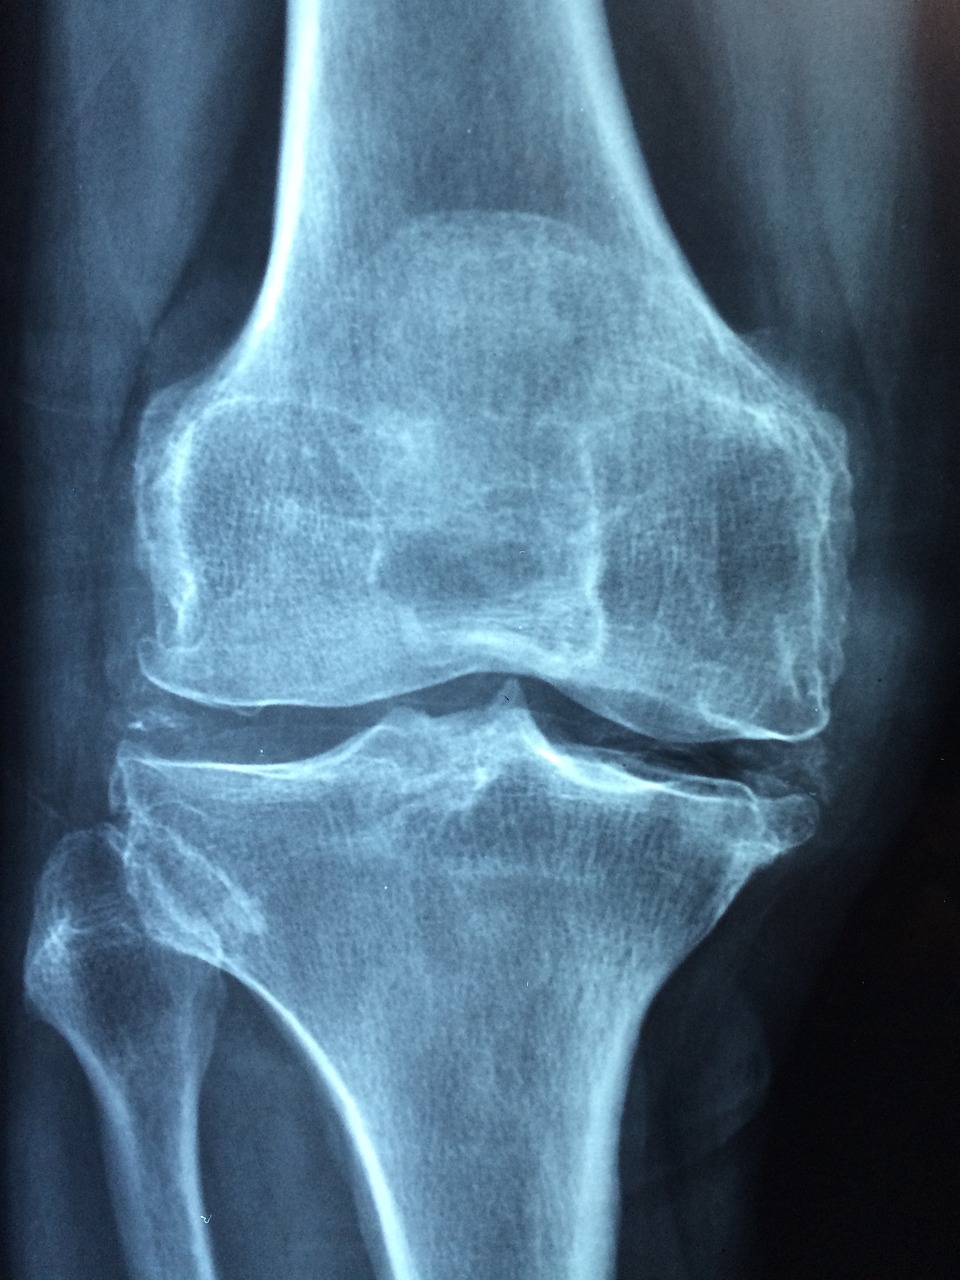

우리의 뼈 건강, 챙기고 계신가요? 뼈 건강은 한순간에 얻어지는 것이 아닙니다. 우리의 몸을 지탱하고 있는 뼈가 약해져서 깨지기 쉽고 골절되기 쉬운 상태를 우리는 골다공증이라고 부릅니다. 골다공증에 대해 알아보고 우리의 뼈 건강을 유지할 수 있는 방법, 골절 위험을 줄이는데 필요한 지식을 갖추는 것은 매우 필요합니다.

골다공증의 초기증상 발견하셨나요? 우리는 시간이 지남에 따라 노화되어가고 있습니다. 사람에 따라 노화속도는 다르겠지만 시간이 지남에 따라 점진적으로 뼈가 약해지면서 그로인한 척추 압박 골절의 증상까지 발견되는 경우도 있습니다. 또한 골절이나 척추뼈가 약해지면서 이로인해 발생하는 지속적인 허리 통증을 증상으로 볼수 있습니다. 특히 노인의 경우 골다공증 증상이라고 볼 수 있습니다. 그 외에 손목과 고관절 또는 서있는 높이에서 넘어지는 등 경미한 충격이나 외상으로 발생하는 골절은 골다공증 증상이라 할 수도 있습니다.

또한 바른자세를 유지하려하여도 구부정한 자세 후만증 또는 허리 휘어짐이 생기는 증상도 발견됩니다. 전반적인 뼈의 힘이 약해지면서 손과 손목의 뼈도 약해지게 되면 손의 힘, 악력이 눈에 띄게 감소 할 수 있습니다.